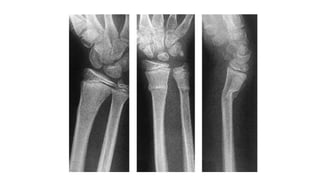

• 4.

Complete fracture • Boneis split into two or more fragments • Transverse • Oblique • Impacted • Comminute